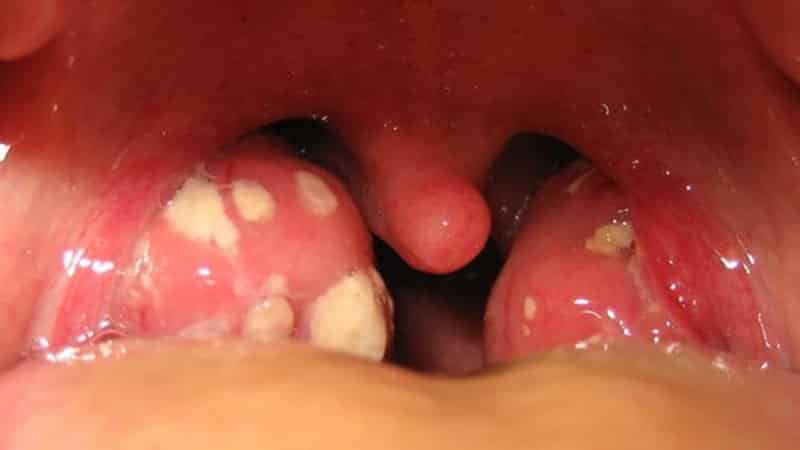

Обратите внимание на изображения выделений:

В это время у пациента появляются белые образования, обладающие неприятным запахом и необычным цветом. Кроме того, больные могут жаловаться на повышение температуры, болезненные ощущения в горле, покраснение слизистой и признаки общей интоксикации.

Белые комки могут вылетать из горла при кашле, чихании, пении или громком разговоре. По своей консистенции они могут быть плотными, упругими или мягкими. Степень их плотности зависит от времени, проведенного в горле, а также от этого фактора зависит и цвет выделений.